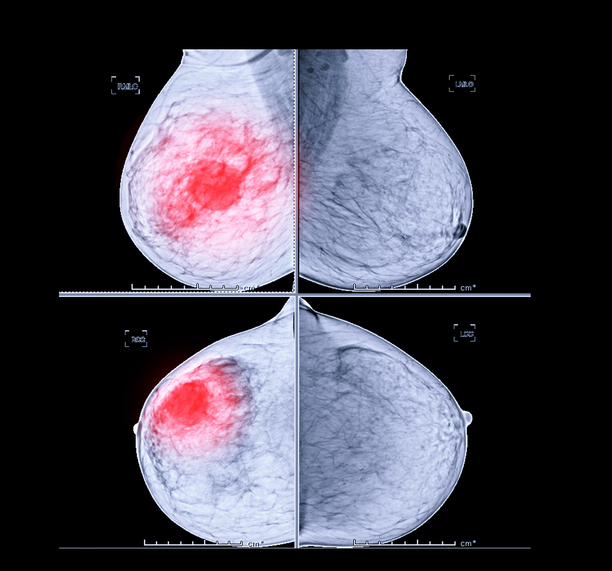

계적으로 여성은 3명 중 1명이 암에 걸린다고 합니다. 여성암 중 갑상선암 다음으로 두 번째로 높은 암이 유방암이라고 하는데, 중년 여성의 암 사망률로는 유방암이 1위라고 합니다. 유방암이란 유방에 나타나는 모든 악성 종양을 통틀어 말하는 것으로 보입니다. 유방암은 유방에 비정상적인 조직이 계속 자라거나 다른 장기에 퍼지는 위험한 병이라고 할 수 있습니다.